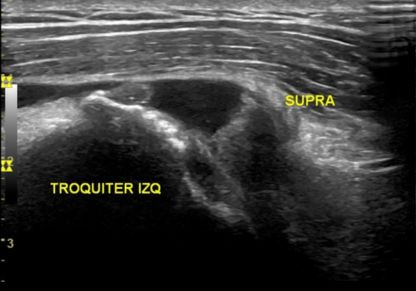

A los pocos días noté una pequeña molestia en el hombro, que atribuí a esos flic-flacs. Pasó el verano y las molestias fueron en aumento. Hace unos días me hicieron una ecografía y me dijeron que ese hombro estaba mal y que no era de ahora. Tenía rotura de un tendón, inflamación de otro y varias calcificaciones; todo ello se había acumulado durante años, y el especialista no podía creer que no me hubiera dolido antes. Posiblemente me haya dolido, pero he tenido recursos suficientes para gestionarlo.

Rotura del tendón supraespinoso